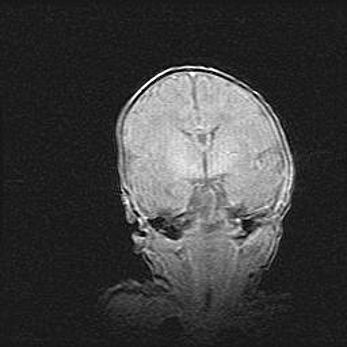

Мальформация Денди-Уокера. Киста задней черепной ямки.

Агенезия мозолистого тела.

Возраст: 2,5 месяца

Вес: 2420 г

Пол: женский

Окружность головы: 37 см

Срок гестации: 32 недели

Мальформация Денди—Уокера — редкий вид патологии ЦНС, представляющий собой врожденный порок развития каудального отдела ствола и червя мозжечка, ведущий к неполному раскрытию срединной (Мажанди) и латеральных (Лушка) апертур IV желудочка мозга. Для этогно синдрома характерна триада симптомов: гипотрофия червя мозжечка и/или полушарий мозжечка, кисты задней черепной ямки, гидроцефалия различной степени. В 70% случаев порок сочетается и с другими аномалиями головного мозга, в частности с агенезией мозолистого тела.